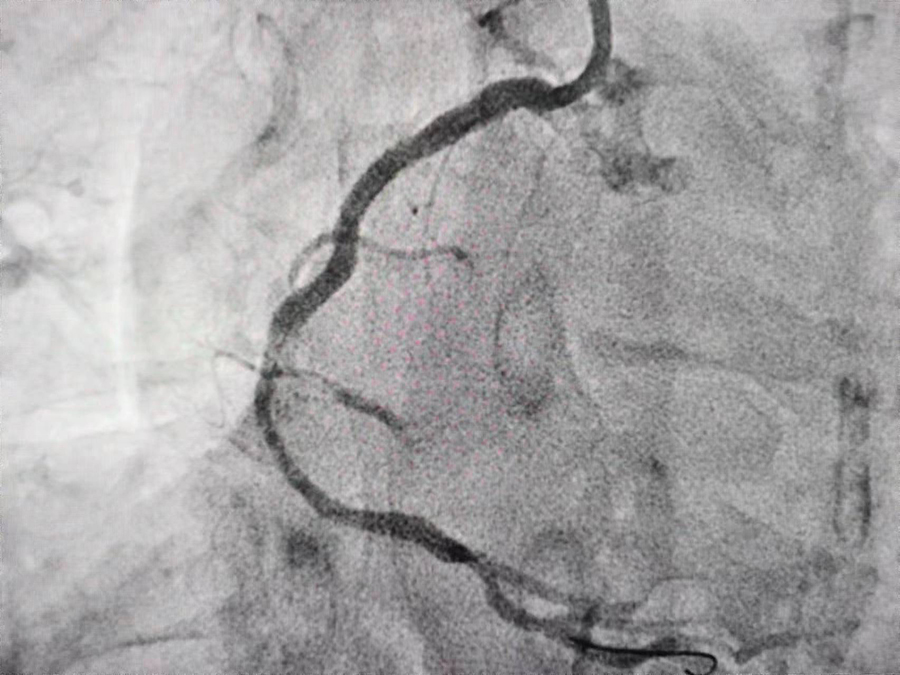

导管室副主任医师孙良为患者安排了造影检查。造影提示:其左侧一支血管闭塞,一支严重狭窄扭曲;右侧一支血管严重狭窄扭曲。考虑到患者冠脉三支病变。经会诊后,医生建议患者进行搭桥治疗。但是由于患者经济条件有限,根据患者身体情况,医生与患者家属协商后,决定为其进行“冠脉造影术+经皮冠状动脉内支架植入术”治疗,助其血运重建。

6月15日10:00,患者被推入导管室接受治疗。导管室内,孙良医生和团队成员在影像的辅助下紧张忙碌着,大家各司其职,精准植入支架,并密切观察患者的身体情况;导管室外,林静姝主任一直陪同家属等待着。经过两个半小时的奋战,介入治疗成功完成。